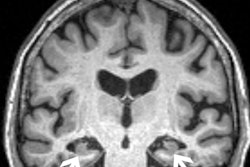

The system includes a whole-body magnetic resonance scanner designed for neonate and infant anatomy, including the head, body, and extremities.

The Ascent3T uses a 3-tesla magnet and addresses the technical limitations of using an adult-size MRI system to image babies. The system is also virtually helium-free and does not require a quench pipe or outside venting.

The design of the Ascent3T was based on learning from over 1,700 infant MRI scans on Cincinnati Children’s prototype systems. In 2023, Eyas installed a research-use-only Ascent3T system within Cincinnati Children's neonatal intensive care unit (NICU).